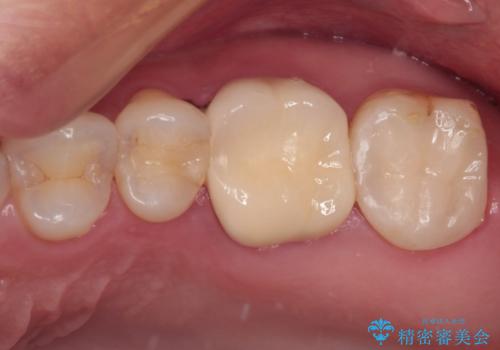

矯正治療が概ね終了した時点で前歯をオールセラミッククラウンにて補綴治療を行い、その後インビザラインにて細かい部分を仕上げていくことしました。

セラミック治療の注意事項(リスク・副作用など)

- 天然歯を削ります

- 硬い素材は天然歯を傷つけてしまう場合があります

- かみ合わせや歯ぎしりが強すぎる方はセラミックが割れてしまう可能性があります

- 自費診療(保険適用外治療)となります